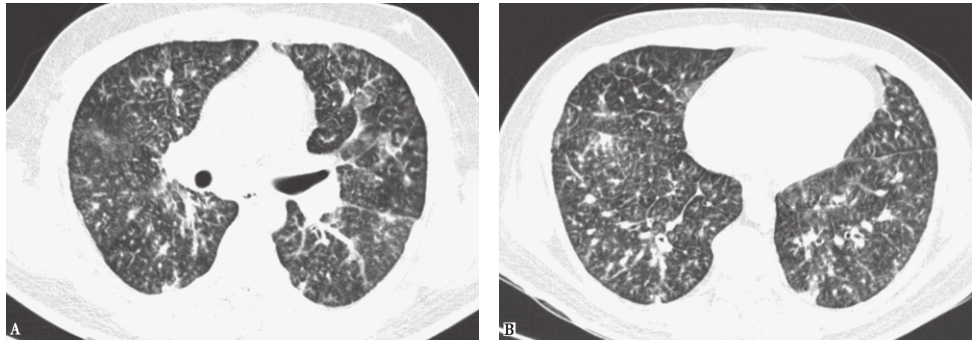

可出现类似胸部CT表现的感染性疾病有血行播散型肺结核、血行播散性真菌感染。血行播散型肺结核急性期胸部CT可见两肺大小、密度、分布“三均匀”的粟粒样结节,多数结节直径<3mm,边缘一般清楚(图3),一般不引起近肺门部的支气管血管束结节;亚急性期则表现为结节大小、分布、密度多不均一,中上肺野多见(图4),部分病灶可融合并产生干酪样坏死、空洞形成。多数患者有结核分枝杆菌感染中毒症状,痰检可发现结核分枝杆菌,结核菌素试验呈强阳性,红细胞沉降率增快等。本例患者无典型结核分枝杆菌感染中毒症状,痰抗酸杆菌阴性,正规抗结核治疗1年余,症状、影像学均无明显改善,故结核分枝杆菌感染可能性不大。

图3粟粒性肺结核胸部CT表现

女性患者,39岁,发热伴胸闷1个月余,病理诊断为粟粒性肺结核。胸部CT可见双肺随机分布的弥漫粟粒性结节

图4肺结核胸部CT表现

女性患者,76岁,反复发热2个月,伴发认知障碍3天,诊断为肺结核、结核性脑膜炎。胸部CT可见双肺分布不均、大小不等的多发结节影